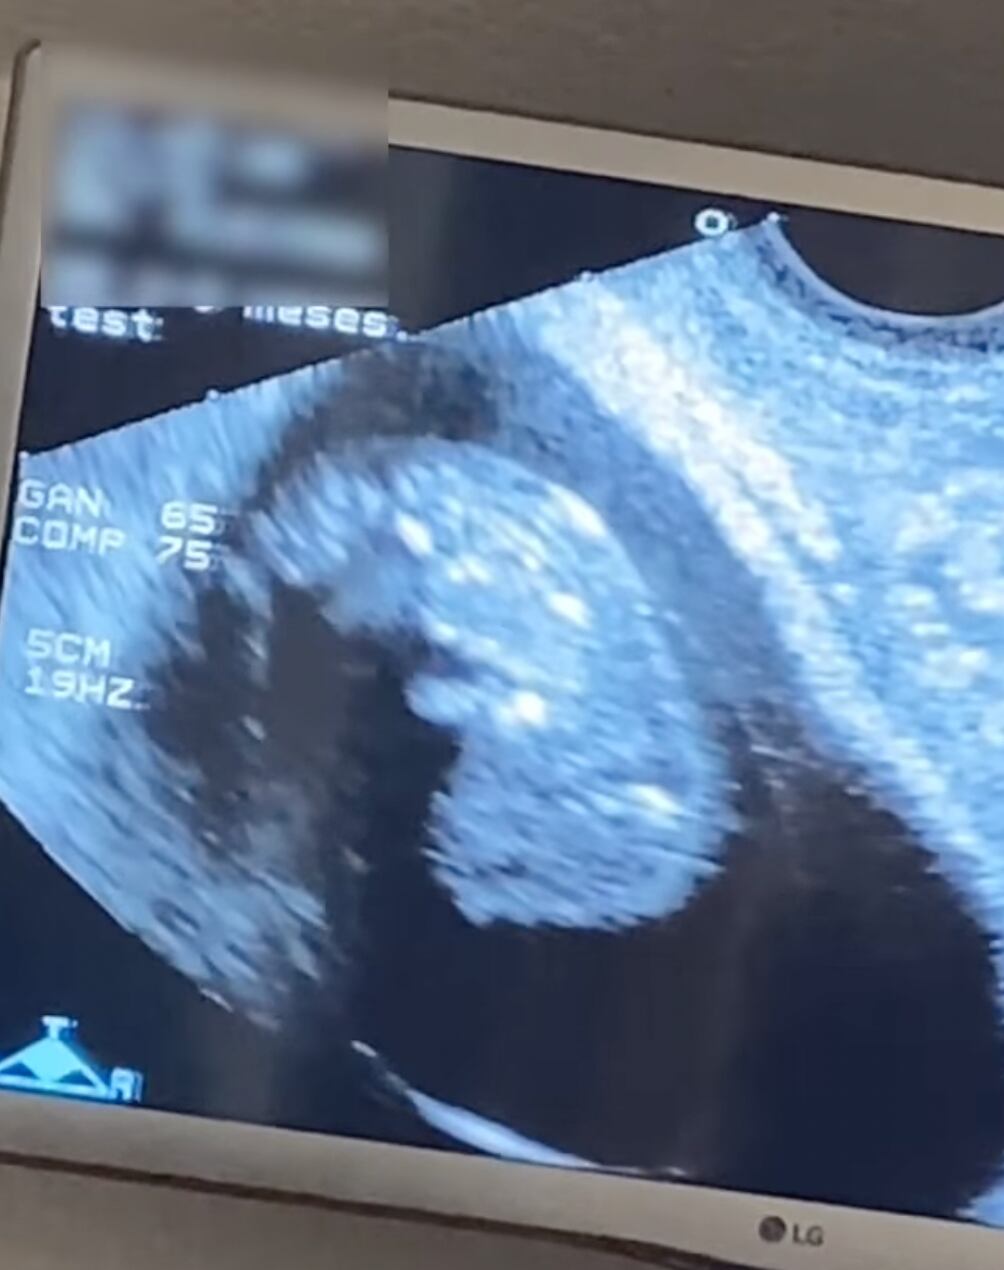

Hasta el momento YosStop no ha dado más detalles sobre su estado, pero presumió un ultrasonido pudo ser tomado cuando tenía alrededor de tres meses de embarazo.